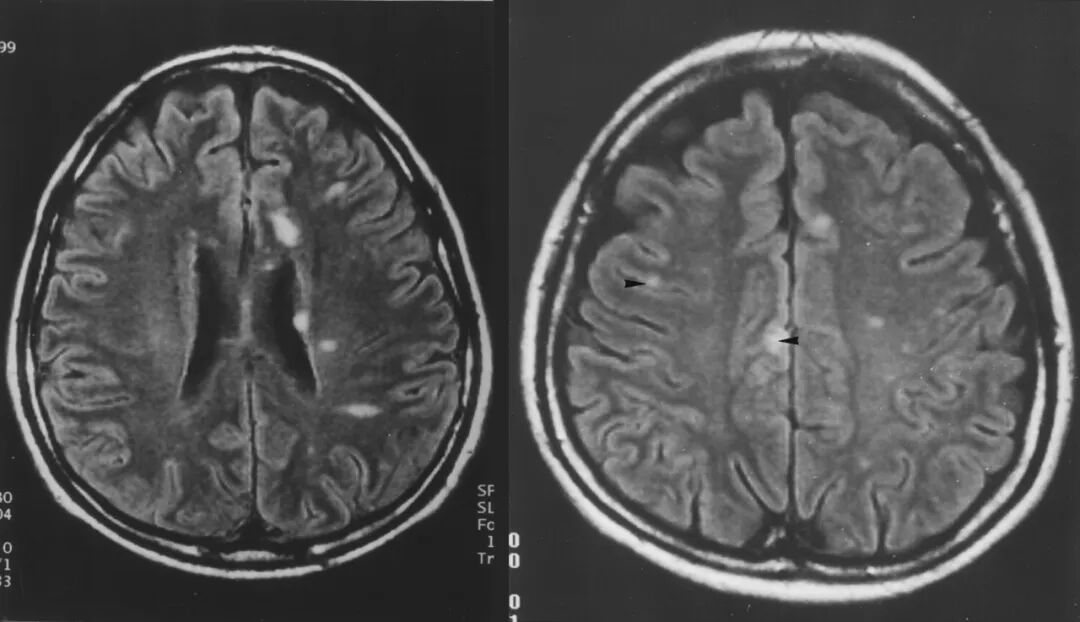

但真正让尼帕病毒“名声在外”的,是它对中枢神经系统的攻击能力。病毒可以穿越血脑屏障,引发脑炎。临床上常见的表现包括意识障碍、抽搐、昏迷,进展速度很快。有些患者在短时间内就会从发热头痛,发展到深度昏迷。

尼帕脑炎患者的脑部病灶(白色部分)。(图/ajronline.org)

即便幸运地活了下来,仍有相当比例的幸存者在康复后出现癫痫等长期神经系统后遗症。世界卫生的调查报告,以及多项随访研究都明确提到,尼帕病毒感染的“远期神经损伤”问题不容忽视。